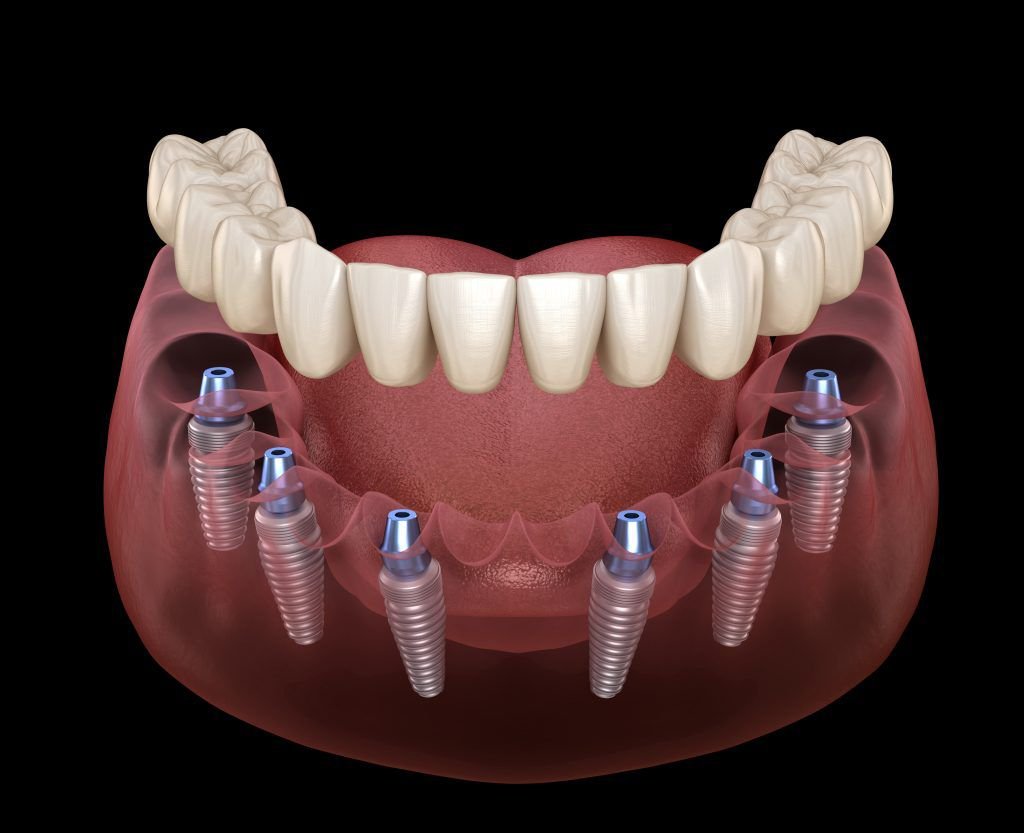

| All-on-4 (per arch) | ₹1,50,000 – ₹3,50,000 |

| All-on-6 (per arch) | ₹2,00,000 – ₹4,50,000 |